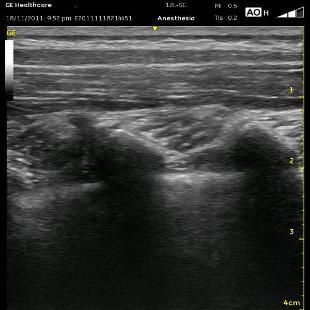

Once I have determined the sites for injection or injections, I start several centimeters laterally in a paramedian plane and follow the ribs medially. After identifying the bright shimmering white comet-tail appearance of the pleura moving with inspirations, watch for the rounded ribs to become more squared and shift slightly cranially. This is the transition from the rib to the transverse process. It can be a very subtle change. If you travel too far medially, the separated squared lines of the transverse process will become one jagged line representing the facet joints and laminae. In the series of images below (ribs, transverse processes then facet joints), the erector spinae muscles can be seen above the two layers of intercostal muscles. Cranial is to the right, and you can tell by the widening of the paravertebral space as you look from left to right.

Once you are appropriately over the transverse processes, angle the probe slightly medially (so that the beam is ‘looking’ laterally). This will allow the Superior Costotransverse Ligament (SCTL) to optimally (or at all) come into view. It is the bright white line just above the pleura in the images above. This is the critical element to recognize. This oblique maneuver is necessary to orient the probe to the ligament at a 90 degree angle because of the rounded nature of the ribs which are diving anterior (deep) as they approach each other at their posterior aspect at the spine. To see it at the most perpendicular angle, you must position the probe obliquely. As mentioned above, the SCTL will be seen going from deep to superficial as it goes caudal to cranial. That is because it attaches between the superficial aspect of the rib and the deep aspect of the transverse process cranial to it. Your goal is to put the needle just deep to the SCTL in the wedge-shaped darkened space just superficial to the pleura.

Remember to insert your needle in a path that matches the oblique tilt of the probe. There is usually a ‘pop’ sensation as you cross the SCTL. It is less prominent if you are too far lateral where the SCTL is contiguous with the less dense internal intercostal membrane, the medial continuation of the internal intercostal muscle. You will want to see the pleura bowing down (deep) in the interspace you are injecting as well as in the adjacent interspaces. If you are too far lateral, you will end up with either an intercostal block or maybe just a small degree of extension cranially and caudally. Whenever I believe this is the case, and it has been a struggle just to get the needle in the correct plane, I will turn my Tuohy bevel 90 degrees toward the spine with the thought that I may be able to make it slide medially instead of laterally. I can’t say that I know if this has been helpful or not, however.